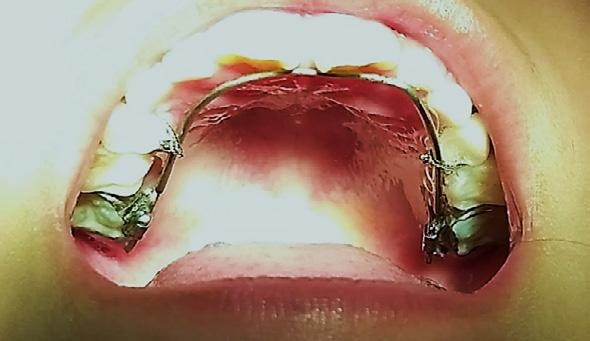

La filosofía Moulin provee la posibilidad de utilizar arcos adaptados a las caras palatinas con una ejecución de fuerza mecánica ligera y controlada, mediante la cual se aplicará una biomecánica de desplazamiento vertical del diente 21(>) y 11. Los alambres de TMA estructuralmente contienen titanio en fase β , molibdeno y zirconio en una estructura fijada a alta temperatura que proporciona unas propiedades elásticas muy singulares e intermedias entre los aceros y las aleaciones típicas del níquel-titanio.

Toma, medición y montaje de modelos de trabajo (Figura 2). En oclusión céntrica se obtiene una sobremordida horizontal positiva de 1 mm con una relación molar clase I. Se confeccionó el arco con un calibre con alambre TMA 0.032 impreso sobre las caras palatinas de los dientes 11 (>) y 21 en el modelo, con el objetivo de ejercer un movimiento de vertical anterior de 2.5 mm sobre los dientes ya en boca. Se colocaron módulos de separadores interdentales y se aplicó flúor. En la cita de inicio de tratamiento, se cementaron las bandas ya con las cajas palatinas soldadas sobre las cuales se posiciono el arco de alambre TMA calibre 32; hay que recordar que es obligatorio

pulir cuidadosamente las puntas del alambre TMA, dejándolas romas para evitar irritación en la lengua de los pacientes, común en pediátricos, así como el adosamiento y calibración de las bandas. Se descansó sobre las caras palatinas el alambre del arco a 3 mm del cíngulo de los dientes 11 y 21, fijándose con alambre número 8, entorchado, sujetando con amarre firme, circunscrito a la corona de los dientes 54 y 64, cuidando de no provocar movilidad, avulsión o situación periodontal negativa (Figura 3), recordando que los omegas de los arcos deben de quedar separados de la mucosa de 1 a 2 mm después de ser ligados para no lesionar la encía.